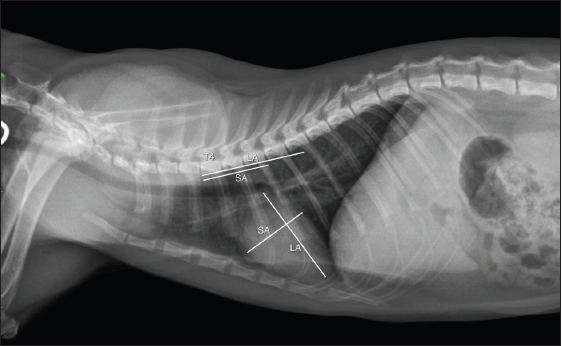

Thoracic radiograph evaluation

The right lateral projection of thoracic radiographs of all included cats in this study was collected as digital information and communication (DICOM) files for measuring the rVHS through DICOM viewer software (Osirix®, Geneva, Switzerland) as shown in Figure 1. The rVHS was examined by measuring the long axis (LA) and the short axis (SA) as described by Lister and Buchanan (2000). The LA and SA were manually measured using a digital caliper and the values were recorded. The LA was the distance from the ventral border of the mainstem bronchus to the cardiac apex. The SA was the widest distance of the heart perpendicular to the LA line. The LA and SA lines were transposed onto the vertebral column and the number of vertebrae beginning from the cranial end plate of the fourth thoracic vertebrae (T4) were recorded as rVHS. All radiographic measurements were performed by the same investigator using the same image archiving PACs system with the DICOM viewer software.

Fig. 1. rVHS measurement methods. rVHS was measured on right lateral thoracic radiograph. LA was the distance from ventral border of the mainstem bronchus to the cardiac apex. SA was the widest distance of the heart perpendicular with the LA line. LA and SA lines were transposed onto the vertebral column and the number of vertebrae beginning from the cranial end plate of the fourth thoracic vertebrae (T4) were recorded as rVHS. rVHS: radiographic vertebral heart score; LA: long axis; SA: short axis; T4: the fourth thoracic vertebrae.